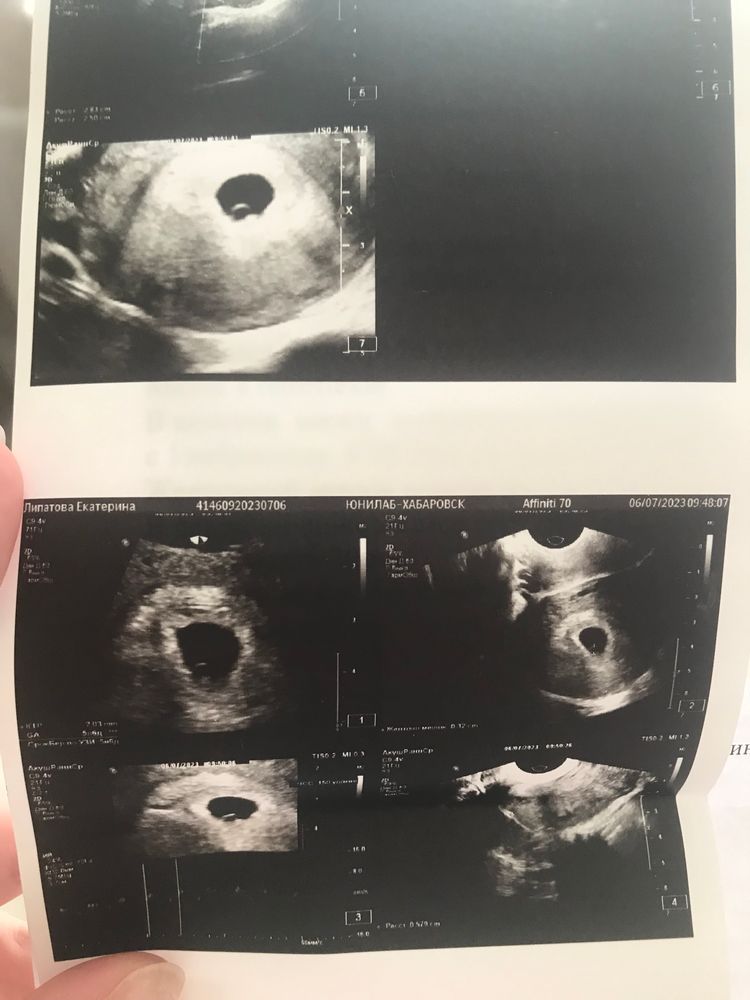

Екатерина, Изображение

Алена, на втором снимке очень отчётливо видно желточный мешок и эмбрион ))